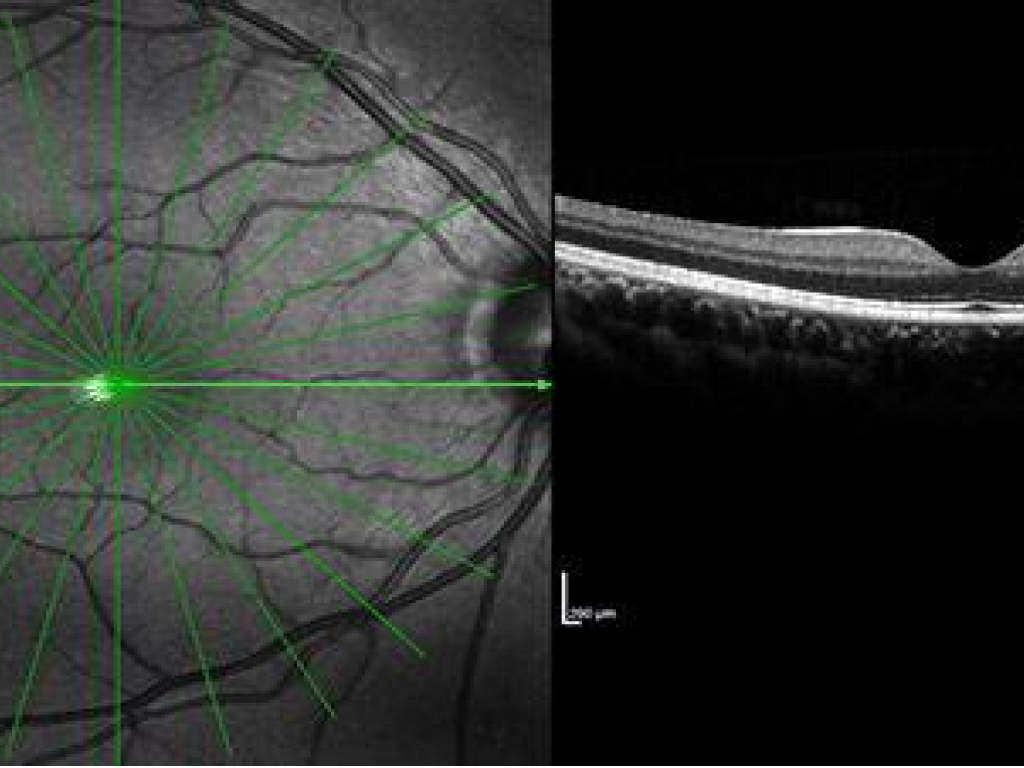

Tomografía de Coherencia Óptica (OCT)

La OCT es una técnica de diagnóstico por imagen avanzada, indolora y no invasiva que captura imágenes detalladas de las capas internas de la retina. Este análisis en profundidad permite:

- Evaluar la mácula y el nervio óptico.

- Detectar patologías de manera temprana.

- Realizar seguimientos precisos en pacientes con enfermedades oculares.